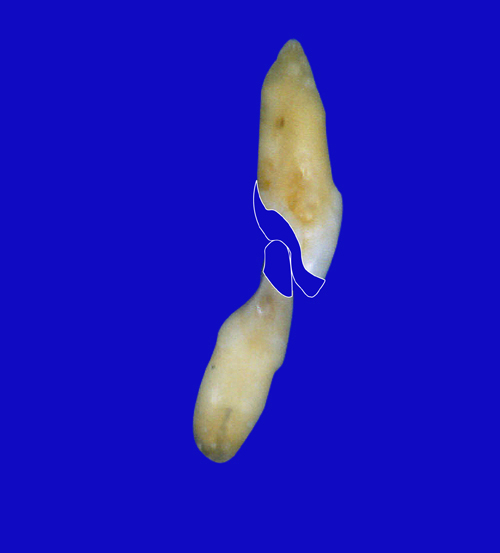

En ciertas áreas del saber humano, el lenguaje confuso o criptográfico Muchas son las técnicas elaboradas para lograr un desgaste selectivo, y numerosos autores han expuesto en su momento variadas formas de lograr una función oclusal fisiológica mediante el ajuste de la misma. Han pasado años desde entonces y, sin embargo, aún hoy, un altísimo porcentaje de profesionales “navega” por el mar de la confusión oclusal, dada la diversidad de conceptos y escuelas, sin lograr arribar a costa alguna donde poder anclar un conocimiento sólido sobre cómo tratar la oclusión Ya se esté realizando una simple obturación, endodoncia, incrustación, radectomía u ortodoncia, la lógica pocas veces, en la mayoría de los casos, vincula un tratamiento con otro, siendo el resultado final el mismo caos inicial; enmascarado por mucho tratamiento profesional. El ajuste oclusal es un medio inicial de proveer al sistema enfermo de: Dicha técnica, que puede ser terapéutica en sí misma; consta de dos etapas, a saber: 1) Ajuste Oclusal por Adición Mediante el estudio de la guía anterior, encargada de efectuar las Disclusiones durante las excursiones mandibulares, podremos observar si ésta es funcional o no. • Marcas de carácter continuo, si en ese recorrido se produce la Disclusión de los sectores posteriores y todo marcha correctamente. FIG 1-2 Si por el contrario observamos: • Marcas de carácter discontinuo, significa que dicha Disclusión se está efectuando por medio de una pieza dentaria posterior a la guía anterior. FIG 3-4-5 (FIGS. 3, 4 Y 5). En la figura 6 las flechas indican, en un caso clínico de análisis oclusal, la presencia de marcas discontinuas que indican Interferencias en Propulsiva. FIG 6-7 Y por último, si existieran: • Abrasiones de las áreas discluyentes en las áreas de diagnóstico de la guía anterior, deberemos aportar material a dicha zona para no permitir el choque lateral de las piezas posteriores (Ajuste Oclusal por Adición) En las imágenes 11 y 12 podemos observar la adición de composite en la punta de un canino derecho, previa la observación de la Faceta Parafuncional remarcada durante el análisis oclusal en el articulador. (FIGS. 8 A 12). 2) Ajuste oclusal por Sustracción o Desgaste Habiendo cumplido ya con la verificación de la funcionalidad de la Guía Anterior, comenzamos los desgastes en céntrica, a fin de lograr un único arco de cierre, guiado eficazmente por la Guía Anterior; es decir: la coincidencia entre Oclusión Habitual y Oclusión en Relación Céntrica. En este caso, intentar gastar dichos puntos, de ser posible sólo en las cúspides de corte o no fundamentales: • Crestas Triangulares Internas, Cúspides Vestíbulares Superiores • y un poco de las Crestas Triangulares Internas, Cúspides (FIGS. 13 A 16). Si la deflección es hacia el lado opuesto, se invierten los desgastes. En las migraciones hacia adelante, las únicas razones posibles están en los puntos estabilizadores (FIG. 17); es decir: -Vertientes Distales de los Rebordes Marginales, Triangulares (FIG 17) (FIG 18 A-B-C-D) Obsérvese cómo, en una boca prácticamente entera, comienzan a “desmoronarse” prismas adamantinos (FIG. 19), como consecuencia de un punto prematuro de contacto, ubicado en la posición de un estabilizador, que provoca la discrepancia horizontal postero-anterior causante de dicho efecto (FIG. 20). FIG 19-20 Dicho punto, será necesario ajustarlo antes de cualquier tratamiento en la zona ¿Cuáles serían las consecuencias si esos incisivos fueran implantados tal como es frecuente observar en múltiples congresos y cursos de implantología, donde el tema de la oclusión no es más que un cuadro polifacético y anecdótico? 14 15 16 17 Todo producto del adelantamiento mandibular Realizados ya los desgastes en céntrica, obteniendo de esta manera un único arco de cierre, es decir, oclusión en relación céntrica, debemos realizar el ajuste de las excéntricas, apoyando la acción de la guía anterior, para lo FIG 22 a. De un lado a otro de un mismo maxilar, la imagen es especular, o sea invertida. b. En hemimaxilares cruzados, la imagen es idéntica. Allí donde existan colisiones entre cúspides, se deberá crear un surco para que dicha cúspide antagonista migre a su través, tanto en el lado de no trabajo, como en el de trabajo y en el de propulsión. FIG 23 Es importante conservar esta parte del surco, ya que si no existieran, los contactos entre cúspides serían en superficie y no puntiformes (fig. 24). FIG 24 1. Obtener un único arco de cierre con coincidencia entre oclusión habitual y relación céntrica. 2. El cierre mandibular debe ser recibido sólo por la tabla premolar-molar. 3. Durante las excursiones funcionales es la guía anterior la que debe sufrir las fuerzas laterales. 4. De cumplirse estas dos premisas debemos obtener libertad de desplazamiento (no confundir con libertad en céntrica) a las piezas posteriores mediante la creación de surcos disclusivos. Examinadas ya las posibles migraciones mandibulares y los desgastes o aposiciones necesarios para poder ocluir en céntrica, es fundamental recordar que, previamente a todo tipo de ajuste, se ha hecho necesario ubicar a la mandíbula en relación céntrica. Para ello debemos utilizar el propio funcionalismo muscular 22 FIG 25 Y esto no significa otra cosa que: piezas dentarias estables en todos los planos del espacio, ATM centrada en la cavidad glenoidea, periodontos sin tensión, músculos en la dimensión de elongación adecuada para un fisiologismo Paz absoluta en la intimidad del Sistema Estomatognático. Y así, como corolario final, es posible establecer una regla de oro similar en importancia a la conocida formula: Forma = Función Ésta es: FIG 26 FUNDAMENTOS NEUROFISIOLÓGICOS DEL REGISTRO DE OCLUSIÓN EN RELACIÓN CÉNTRICA ( ORC) MEDIANTE EL USO DE LAMINILLAS DE LONG CUADRO

Esta migración generalmente se acompaña de anomalías en el sector anterior (FIG. 18).

anterior, ya que si no liberamos la causa, el efecto se seguirá produciendo y, a

pesar de que la abrasión de0estos incisivos superiores es apenas el comienzo de una futura bruxomanía, invito al lector, sea éste especialista en prótesis, operatoria dental, cirugía bucal, etc., a pensar:

Otro de los fenómenos que es frecuente observar es la respuesta

tanto del maxilar superior, “abanicando” sus piezas,

fenómeno que denominamos DISPERSIÓN (fig. 21), como del

maxilar inferior, provocando lo que los ortodoncistas durante

décadas acusaron a la erupción del 3er. molar, encimando

todo el grupo incisivo, fenómeno que denominamos APIÑAMIENTO

FIG 21